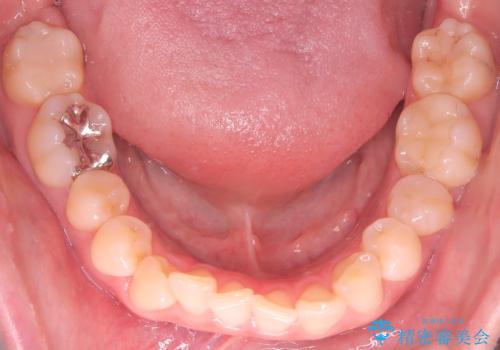

- 下の前歯のデコボコ(叢生)を気にされてご来院されました。精密な検査の結果、下の前歯を並べるスペースが不足していることが判明。患者様のご希望から、透明で目立ちにくい**インビザライン(マウスピース矯正)による治療計画を立案しました。主に歯の側面をわずかに削るIPR(歯間乳頭保護下ストリッピング)**などでスペースを確保し、下の前歯の叢生を解消することを目指します。

今回の矯正治療では、透明なマウスピース型の装置インビザラインを使用しました。目立たず、取り外しが可能なため、日常生活にほとんど影響なく治療を進めることができました。治療は、緻密に計算された計画に基づき、IPRなどで必要なスペースを確保しながら、下の前歯をスムーズに移動。これにより、長年の悩みであった下の前歯のデコボコが解消され、清掃しやすい、整った歯並びを獲得していただけました。